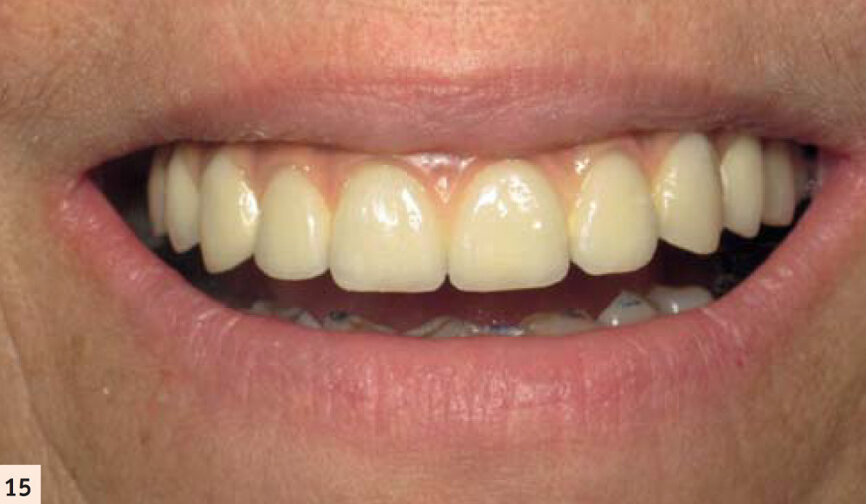

La céramique est maquillée pour s’approcher de l’aspect de dents naturelles. Une fausse gencive rose permet de palier au manque tissulaire préalable (Figs. 14, 15 et 16).Notre patiente a retrouvé ses dents et ne sera restée sans denture fixe que quelques heures. Les suites opératoires auront été minimes et la durée totale du traitement été de 4 mois.

Sourire de notre patiente.